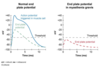

Cerebral Blood Flow Regulation